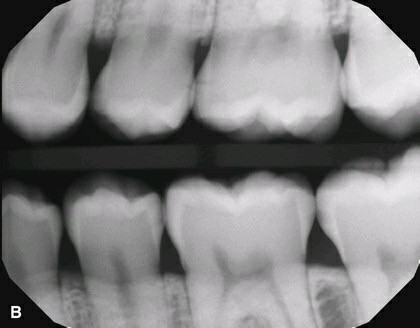

2. In the X ray bellow for which jaw periodontal bone loss is evident?